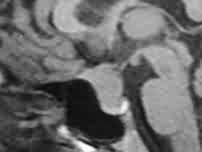

Diaphragm sella

meningioma-MRI